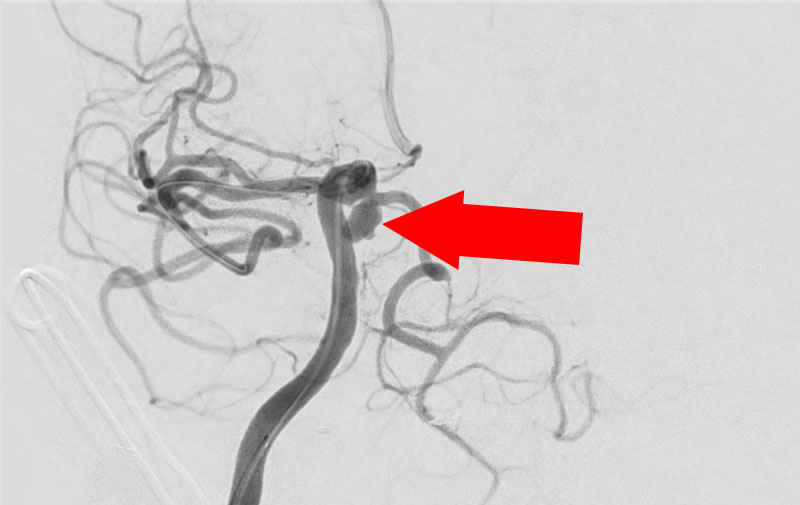

No.1631 手術前